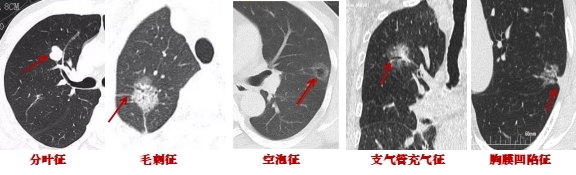

1.結(jié)節(jié)的形態(tài)變化:肺結(jié)節(jié)持續(xù)存在且逐漸增大、密度逐漸增高,惡變可能性大,短期內(nèi)結(jié)節(jié)大小急劇變化的多為良性。若結(jié)節(jié)8mm~15mm,有分葉、毛刺、胸膜牽拉、含氣細支氣管征和小泡征、偏心厚壁空洞這些CT惡性征象,大概率是惡性的。

2.結(jié)節(jié)的密度:純磨玻璃肺結(jié)節(jié)惡性概率相對較低,若伴有實性成分且實性成分逐漸增多,惡變可能增大。混合性磨玻璃結(jié)節(jié)多數(shù)為原位癌或早期肺癌。

3.結(jié)節(jié)與血管的關(guān)系:如果肺結(jié)節(jié)內(nèi)部有血管匯入,周邊有血管伴行,且血管扭曲、增粗、變細或被中斷,往往提示惡性。